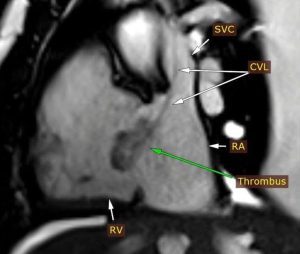

وأضاف الدكتور مجدي القاضي عميد كلية الطب البشري ورئيس مجلس اداره المسشفيات الجامعيه ان التقرير الطبي اوضح بعد إجراء فحوصات الإيكو للقلب، تبين اشتباه وجود ورم بالأذين الأيمن وعلى الفور تم تحويل المريض الى وحدة التصوير الطبى للقلب واجراء رنين مغناطيسى على القلب وتبين ان المريض يعانى من التهابات بعضلة القلب وتواجد جلطة بالاذين الايمن وتم تشخيص الحالة بدقة وتلقى العلاج المناسب بقسم امراض القلب والاوعيه الدمويه.